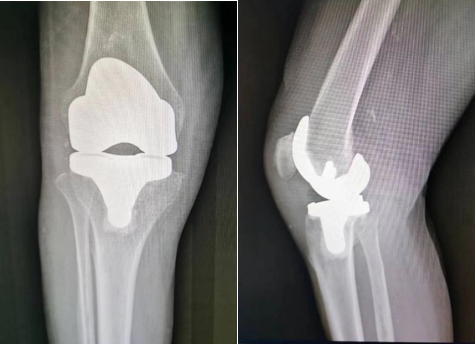

我院骨科从很早就关注到了骨关节各类疾病问题,并率先在我市开展了肩、髋、膝、踝多项高难度关节置换手术。我院骨科于2011年开始向关节置换微创治疗方向发展,率先在我市开展了膝关节单髁置换术、内轴膝全膝关节置换术、髋关节SuperPATH入路微创置换术等高精尖手术,年手术量居我省前列,手术效果良好,群众反馈满意。同时,在治疗上,遵循骨关节病阶梯治疗、个体化治疗的指导思想,在提高手术技术的同时,依然重视保守治疗、微创关节镜治疗等手段,强调疾病的预防和康复,即不延误病情,也不过度医疗。未来几年内,骨科将引进3D打印技术和数字化机器人技术辅助关节手置换术。